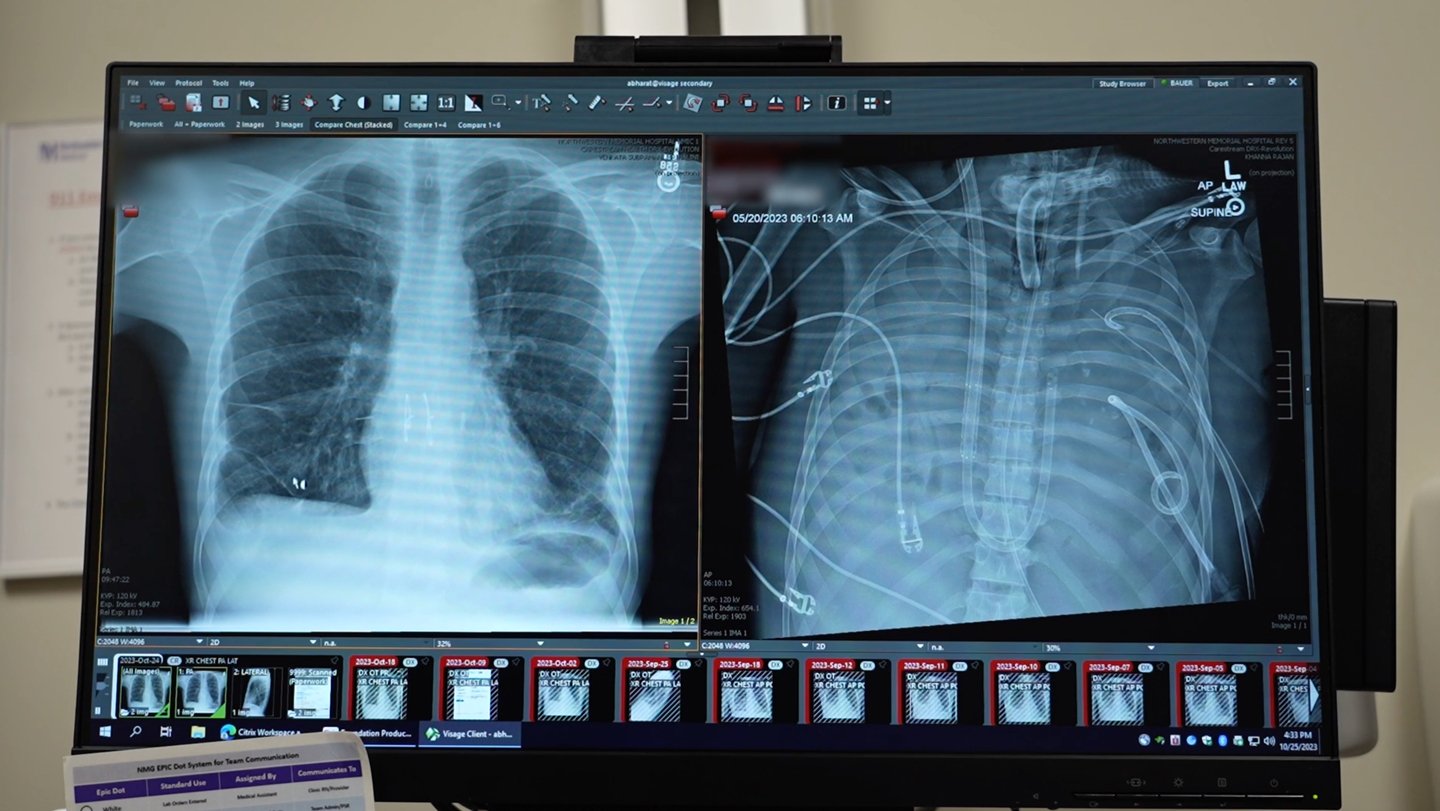

So Bharat and colleagues removed the diseased lungs and hooked the man to the artificial lung the team devised. The system takes blood from the right side of heart, puts it through a pump to add oxygen and take out carbon dioxide as the lungs would, then shunts the blood to the left side of the heart to be pumped through the body. That system maintains normal heart function as well as providing oxygen.